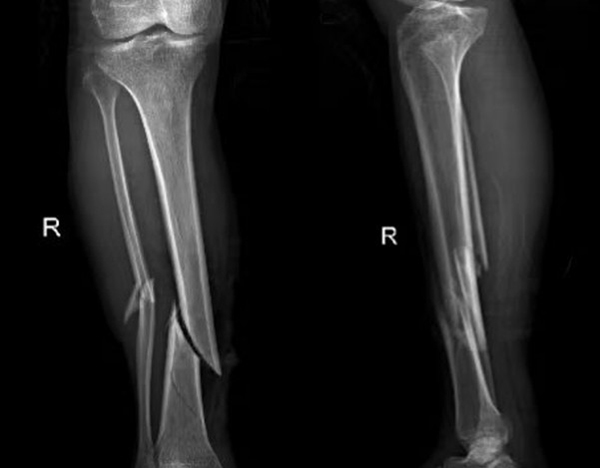

比如外傷患者,排查有無(wú)四肢骨折,X光片是首選,因?yàn)樗芸焖偾逦@示骨骼的連續(xù)性;而檢查關(guān)節(jié)內(nèi)的軟組織(如韌帶、半月板),則需要靠MRI,CT對(duì)此幾乎“無(wú)能為力”。所以,別主動(dòng)要求“升級(jí)”檢查,聽(tīng)從醫(yī)生的專(zhuān)業(yè)建議,才能既準(zhǔn)確又高效。